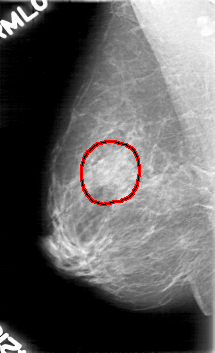

RIGHT_CC LINES 5176 PIXELS_PER_LINE 2896 BITS_PER_PIXEL 12 RESOLUTION 43.5 OVERLAY

FILE: D_4023_1.RIGHT_CC.OVERLAY

TOTAL_ABNORMALITIES 1

ABNORMALITY 1

LESION_TYPE MASS SHAPE OVAL MARGINS OBSCURED

ASSESSMENT 0

SUBTLETY 2

PATHOLOGY BENIGN

TOTAL_OUTLINES 1

BOUNDARY